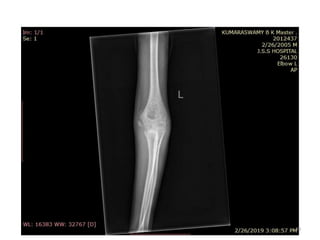

Elbow joint

• Secondary ossification Centres : (3 bones; 6 Ocs)

Capitulum (C) - appearance - 1 year of life

Head of Radius (R)– appearance -4 to 5 years

Medial Epicondyle (ME)

Appearance – 5 to 6 years

Fusion – 16 to 17 years

Trochlea (T) – appearance – 9 to 11 years

Olecranon Process of Ulna (OP)

Appearance - 8 to 9 years

Fusion- 16-17 years

Lateral Epicondyle(LE) – 11 to 12 years

Conjoint (Composite)Epiphysis (CE) [fusion of C+T+LE]

Formation – 14 to 16 years

Fusion – 16-17 years

Note: Fusion of O.Centres at elbow joint is 16-17 years in male, 15-16 years in female

Elbow joint • Secondaryossification Centres : (3 bones; 6 Ocs) Capitulum (C) - appearance - 1 year of life Head of Radius (R)– appearance -4 to 5 years Medial Epicondyle (ME) Appearance – 5 to 6 years Fusion – 16 to 17 years Trochlea (T) – appearance – 9 to 11 years Olecranon Process of Ulna (OP) Appearance - 8 to 9 years Fusion- 16-17 years Lateral Epicondyle(LE) – 11 to 12 years Conjoint (Composite)Epiphysis (CE) [fusion of C+T+LE] Formation – 14 to 16 years Fusion – 16-17 years Note: Fusion of O.Centres at elbow joint is 16-17 years in male, 15-16 years in female 35

ELBOW JOINT All OCsAppeared and fused (>16-17 years) 36